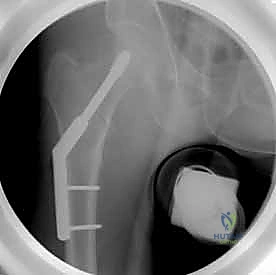

التثبيت بالمسامير المجوفة عبر الجلد (Percutaneous Cannulated Screws): ثورة في جراحة العظام

تُعد تقنية التثبيت باستخدام المسامير المجوفة (Cannulated Screws) المعيار الذهبي لعلاج كسور عنق الفخذ غير المزاحة (Garden I & II) لدى جميع الأعمار، والكسور المزاحة التي يمكن ردها بنجاح لدى الشباب والبالغين.

مميزات التثبيت عبر الجلد (Percutaneous Technique)

- تدخل جراحي طفيف (Minimally Invasive): لا يتم عمل شق جراحي كبير لفتح العضلات والأنسجة، بل يتم إدخال المسامير عبر شقوق جلدية صغيرة جدًا (حوالي 1-2 سم لكل مسمار).

- الحفاظ على التروية الدموية: عدم فتح محفظة المفصل يقلل من خطر الإضرار بالأوعية الدموية المتبقية التي تغذي رأس الفخذ.

- ألم أقل بكثير: نظرًا لعدم قطع العضلات الكبيرة، يكون الألم بعد العملية في حده الأدنى.

- شفاء أسرع: خروج أسرع من المستشفى وتأهيل حركي مبكر.